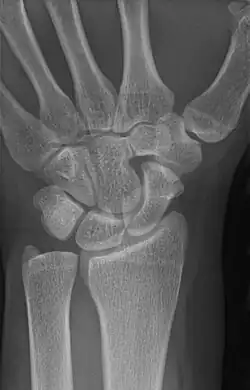

| An example of a lunotriquetral coalition, the most commonly fused carpal bones | |

The lunate and triquetral bones are the most common carpal bones to fuse together, resulting in a lunotriquetral coalition in 1% of people. 60% of patients with a lunotriquetral coalition will have it bilaterally.[1] Among isolated incidents the capitate and hamate bones are the next most common to fuse followed by the pisiform-triquetrum, trapezium-trapezoid, scaphoid-capitate, and triquetrum-hamate.[3]